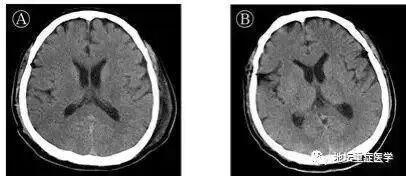

06、中樞神經

3月4日,地壇醫院披露,其收治的一例56歲新冠肺炎患者,通過基因測序證實腦脊液中存在SARS-CoV-2病毒,臨床診斷為病毒性腦炎,患者中樞神經系統受病毒侵襲。 這一情況在全球尚屬首例。

ICU主任劉景院:“患者出現意識障礙,一定要考慮病毒有可能攻擊中樞神經系統。”

4月3日,《國際傳染病雜誌》上一份來自日本的研究報告:在一名患腦膜炎和腦炎的COVID-19患者的腦脊液中發現了SARS-CoV-2,這表明該病毒可以入侵中樞神經系統。